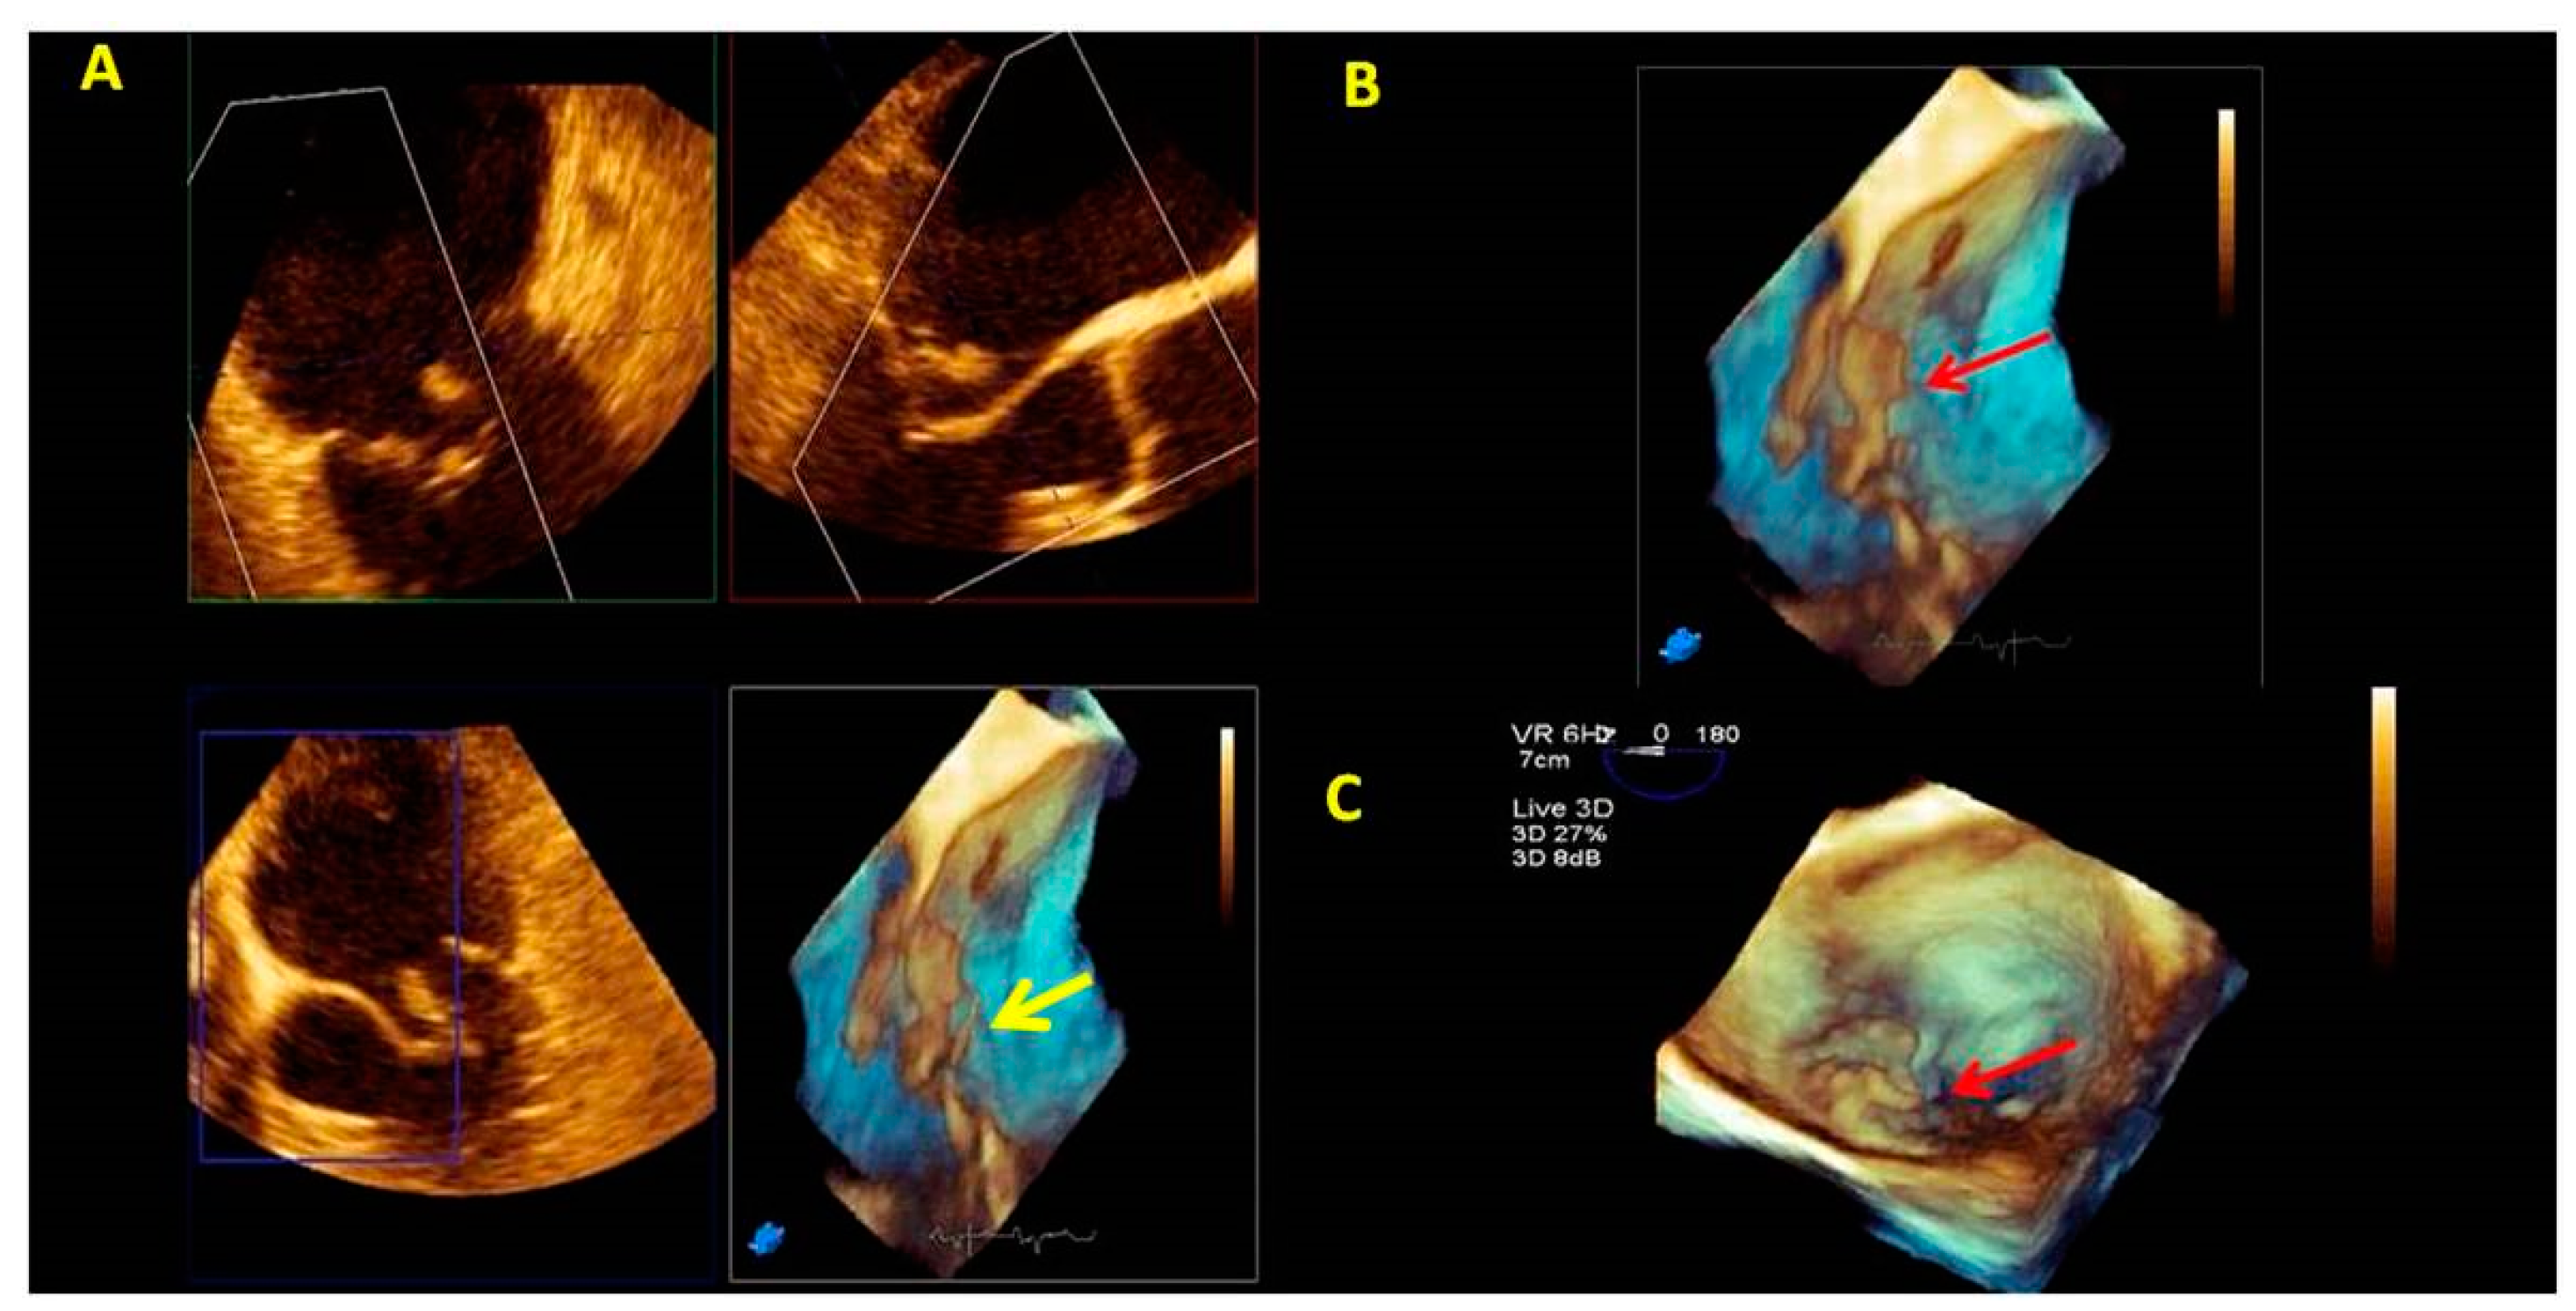

3.1. Anatomical Characterization